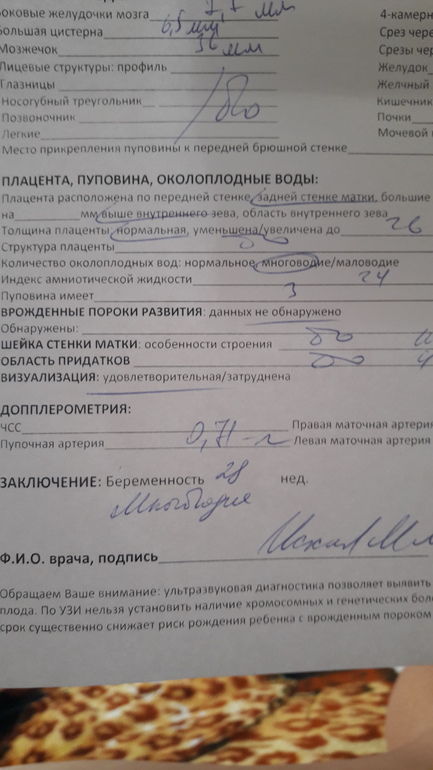

Многоводие при беременности: симптомы и лечение